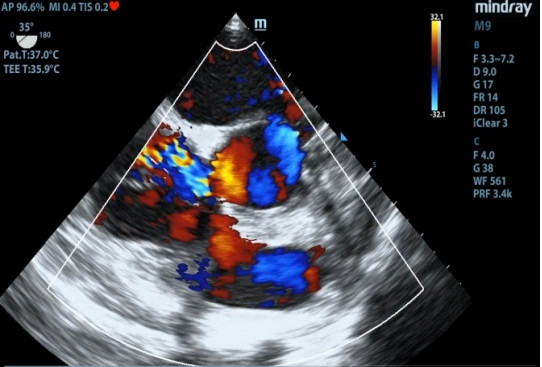

1 资料与方法患者女性,19岁,因“突发胸痛14 h”入院。患者14 h前无明显诱因出现胸骨后疼痛,呈紧缩感,伴有胸闷、呼吸困难,间断咳嗽。近期有听力下降、腹泻病史。8 h前就诊于外院时查体:体温测不出,Bp 53/36 mmHg(1 mmHg=0.133 kPa),呼吸40次/min, 脉搏137次/min,SPO2 93%,神志淡漠,全身皮肤湿冷,黏膜无黄染及出血点,颈静脉无怒张。听诊双肺呼吸音粗,可闻及满肺湿啰音,心音不清,腹部查体无异常,双下肢足背动脉搏动对称。化验结果提示WBC 29.3×109/L,NE 85.4%,TnT 93 ng/L,pro-BNP 2 047 pg/mL,PCT 0.11 ng/mL, 血气分析:pH 7.349,PCO2 31.2mmHg,PO2 67.2 mmHg,HCO3- 17.2 mmol/L,Lac 5.7 mmol/L。心电图提示:窦性心动过速、AVR导联ST段抬高,余导联ST段压低;床旁心脏超声提示EF 52%,二尖瓣中度返流、三尖瓣中重度返流,未见室壁节段性运动性异常。考虑心源性休克,原因尚不明确,给予机械通气、血管活性药物、补液等抗休克治疗,同时联系本院急诊ECMO团队,本院急诊ECMO团队到达现场后,患者突然出现室颤,给予胸外按压及电除颤后逐渐恢复窦律,立即进行V-A ECMO上机指征及预后评分SAVE评分评估,符合V-A ECMO上机适应证,约30 min成功上机运转,流量3.5 L/min,复查外周动脉血气分析: pH 7.305,PCO2 21 mmHg,PO2 73.4 mmHg,HCO3- 10.5 mmol/L,Lac 8.4 mmol/L。后转运至本院急诊病房,转运途中行生命体征、血气分析、ACT等常规监测,至病房后患者ECMO支持下血压仍需大剂量血管活性药物维持且脉压差较小,观察ECMO动静脉管路颜色极为接近,床旁经胸心脏超声提示主动脉瓣重度返流,为明确原因立即行急诊CT检查及床旁经食道超声心动图检查。本院肺CT(图 1)提示肺水肿,床旁经胸心脏超声提示主动脉瓣大量返流但心室收缩可,请超声影像科进一步行床旁经食道超声检查提示无冠窦呈瘤样凸向右房侧,瘤壁上可见宽约0.6 cm破口;主动脉瓣舒张期无冠瓣脱向左室流出道侧(图 2、图 3)。立即请心血管外科会诊,急诊行主动脉瓣机械瓣膜置换术+主动脉窦修补术+房间隔造口术+主动脉球囊反搏置入术+心脏起搏器置入术,术中探查与经食道超声所见相符(图 4、图 5),考虑左心功能差,左心压力较高,行房间隔造口术。术后复查胸片肺水肿基本消失(图 6),继续呼吸机与ECMO支持,因患者肺功能良好,自主呼吸良好,为减少呼吸机相关肺损伤、呼吸机相关肺炎等发生,术后第4天神志清醒后拔除气管插管,机械通气减轻左心前后负荷的作用去除后,继续ECMO与IABP支持,ECMO增加左心后负荷时IABP可降低左室后负荷,达到左心减压的目的,术后第10天心功能恢复,下调ECMO流量后循环可维持,予以撤离ECMO,术后第12天撤离IABP,后停用肝素持续泵入抗凝,达肝素皮下注射联用华法林口服抗凝3 d后,单用华法林口服抗凝,维持INR达标,在康复期间患者活动时左下肢疼痛,左侧足背动脉搏动减弱,下肢动静脉超声提示左侧股浅动脉血栓形成,期间增加华法林剂量后血栓未见明显变化,后行下肢股浅动脉切开取栓术,术后33 d患者完全康复顺利出院。

| 图 2 经食道超声心动图 |

| 图 3 经食道超声心动图 |

主动脉根部造影为诊断主动脉窦瘤的“金标准”[10], 但本例患者生命体征不稳定,外出检查需携带呼吸机及ECMO机器,转运风险较大,因此采用床旁心脏超声检查是非有创检查的最佳手段之一。本案例外院经胸心脏超声提示三尖瓣中重度返流,入院后床旁经胸心脏超声仅发现主动脉瓣重度返流,仍无法明确心源性休克原因,联系超声影像科通过经食道超声心动图发现无冠窦瘤破裂入右心房才最终明确诊断。主动脉窦瘤的诊断需要技术高超且临床经验丰富的超声科医生,也反映出急诊科医生需学习掌握经食道超声心动图技术。